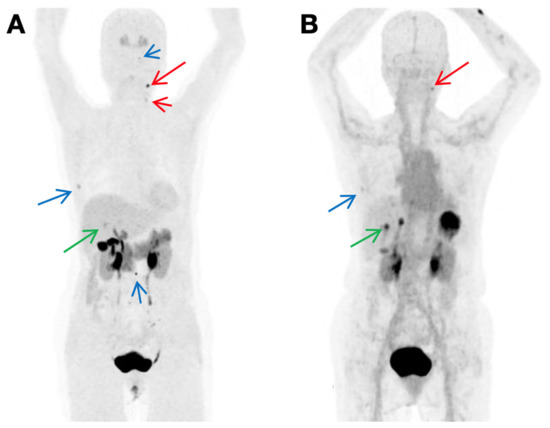

- Bodet-Milin, C.; Faivre-Chauvet, A.; Carlier, T.; Rauscher, A.; Bourgeois, M.; Cerato, E.; Rohmer, V.; Couturier, O.; Drui, D.; Goldenberg, D.M.; et al. Immuno-PET Using Anticarcinoembryonic Antigen Bispecific Antibody and 68Ga-Labeled Peptide in Metastatic Medullary Thyroid Carcinoma: Clinical Optimization of the Pretargeting Parameters in a First-in-Human Trial. J. Nucl. Med. 2016, 57, 1505–1511. [Google Scholar] [CrossRef]

- Bodet-Milin, C.; Bailly, C.; Touchefeu, Y.; Frampas, E.; Bourgeois, M.; Rauscher, A.; Lacoeuille, F.; Drui, D.; Arlicot, N.; Goldenberg, D.M.; et al. Clinical Results in Medullary Thyroid Carcinoma Suggest High Potential of Pretargeted Immuno-PET for Tumor Imaging and Theranostic Approaches. Front. Med. 2019, 6, 124. [Google Scholar] [CrossRef]